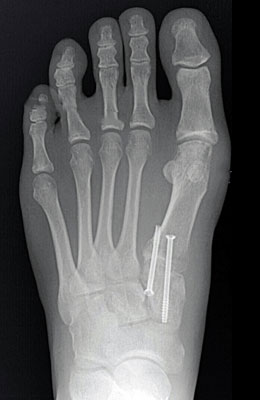

Before

After

Lapidus Forever Bunionectomy™

In this Lapidus procedure, the joint behind the great toe joint, the 1st metatarsophalangeal joint, is fused together with the bunion in a more corrected position. Notice the improved alignment of the great toe joint. 2 screws were used to fixate the bones together and facilitate it towards fusion.